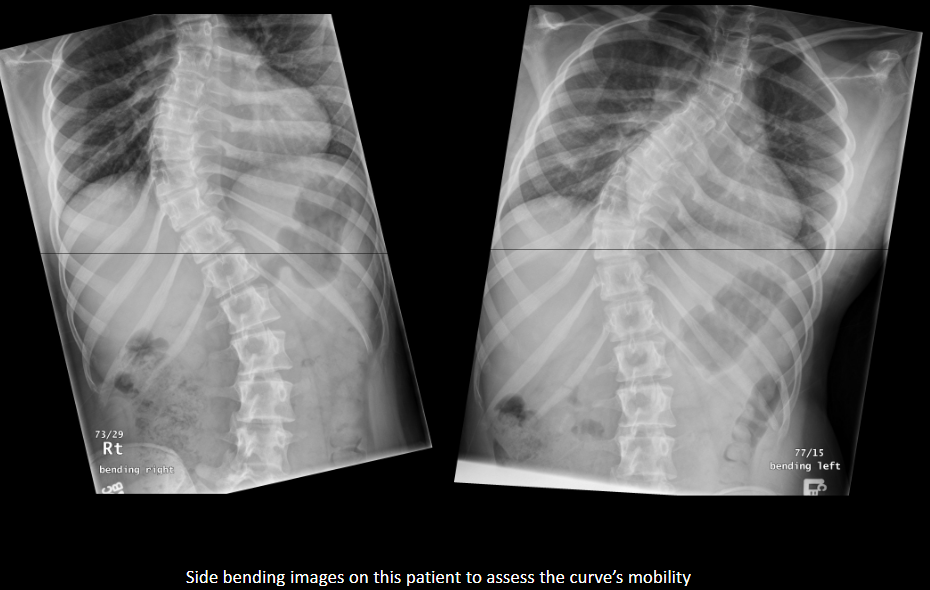

How can you distinguish structural from non-structural scoliosis on side-bending?

Structural scoliosis does not correct with side bending; non-structural scoliosis to a reasonable extent corrects.

What assessment quantifies curve magnitude?

Cobb method.